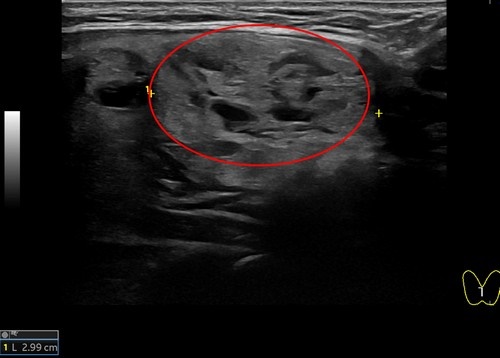

日前,一位51歲女性病人因頸部中間部位腫大來花蓮慈濟醫院影像醫學部施于泰醫師門診,經以超音波檢查,發現右邊有一5.15公分結節,另一個結節靠近甲狀腺峽部約2.99公分;在以細胞學穿刺檢查後為良性結節。病人在接受甲狀腺消融術治療後,隔天即出院恢復正常生活,且一週後已明顯消腫,無副作用發生。

左圖:這位女病患,右側5.15公分結節微波消融前,超音波影像。(施于泰提供)